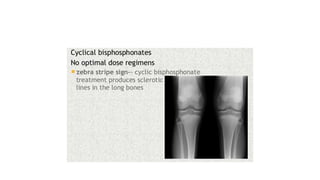

This document discusses a disease and its investigation and management. It begins by introducing Dr. Aniket Wankhede from MGIMS Sevagram and asks what the disease is. It then asks how the disease happens and discusses its causes. Next it asks how the disease appears on x-rays and describes symptoms some people experience living with it. Finally, it asks how the disease will be investigated and managed.